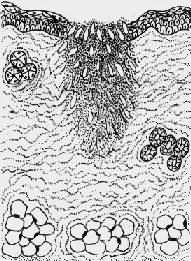

2.二期愈合(healing by second intention) 见于组织缺损较大、创缘不整、哆开、无法整齐对合,或伴有感染的伤口。这种伤口的愈合与一期愈合有以下不同:①由于坏死组织多,或由于感染,继续引起局部组织变性、坏死,炎症反应明显。只有等到感染被控制,坏死组织被清除以后,再生才能开始。②伤口大,伤口收缩明显,从伤口底部及边缘长出多量的肉芽组织将伤口填平。③愈合的时间较长,形成的瘢痕较大(图2-6)。

1.创口大,创缘不整,组织破坏多

2.伤口收缩,炎症反应重

3.肉芽组织从伤口底部及边缘将伤口填平,然后表皮再生

4.愈合后形成疤痕大

图2-6 创伤二期愈合模式图